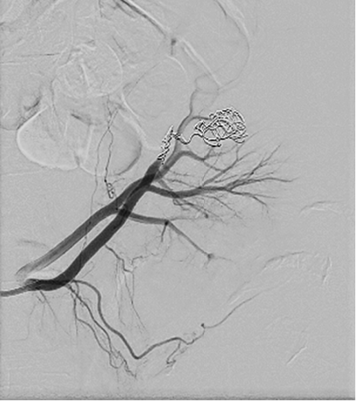

Right femoral artery was punctuated under local anesthetic. Inferior segmental artery was selectively catheterized and pseudoaneurysm was visualized. A microcatheter was inserted into segmental branch (Figure 4).

Figure 4. Renal pseudoaneurysm catheterized and visualized using contrast solution